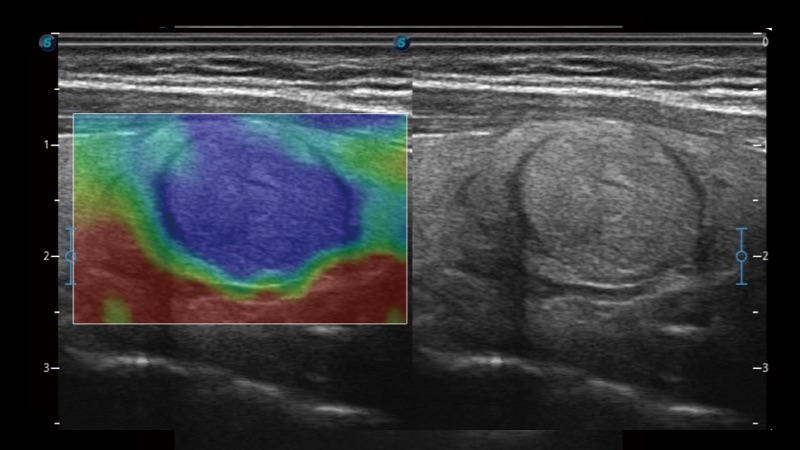

開立醫(yī)療通過不斷的技術(shù)創(chuàng)新,為大眾的生命健康提供持續(xù)關(guān)愛。P12 Plus采用全新一代超聲成像平臺,新平臺旨在將真實(shí)還原組織解剖結(jié)構(gòu)作為首要目標(biāo)。平臺采用全新集成化硬件模塊,搭載新一代芯片,系統(tǒng)性能得到大幅提升,為您的診斷提供了豐富的臨床信息。優(yōu)異的圖像表現(xiàn),豐富的探頭配置,全面的應(yīng)用功能,為您日常診斷提供了可靠的助手。

彩色多普勒超聲診斷系統(tǒng)